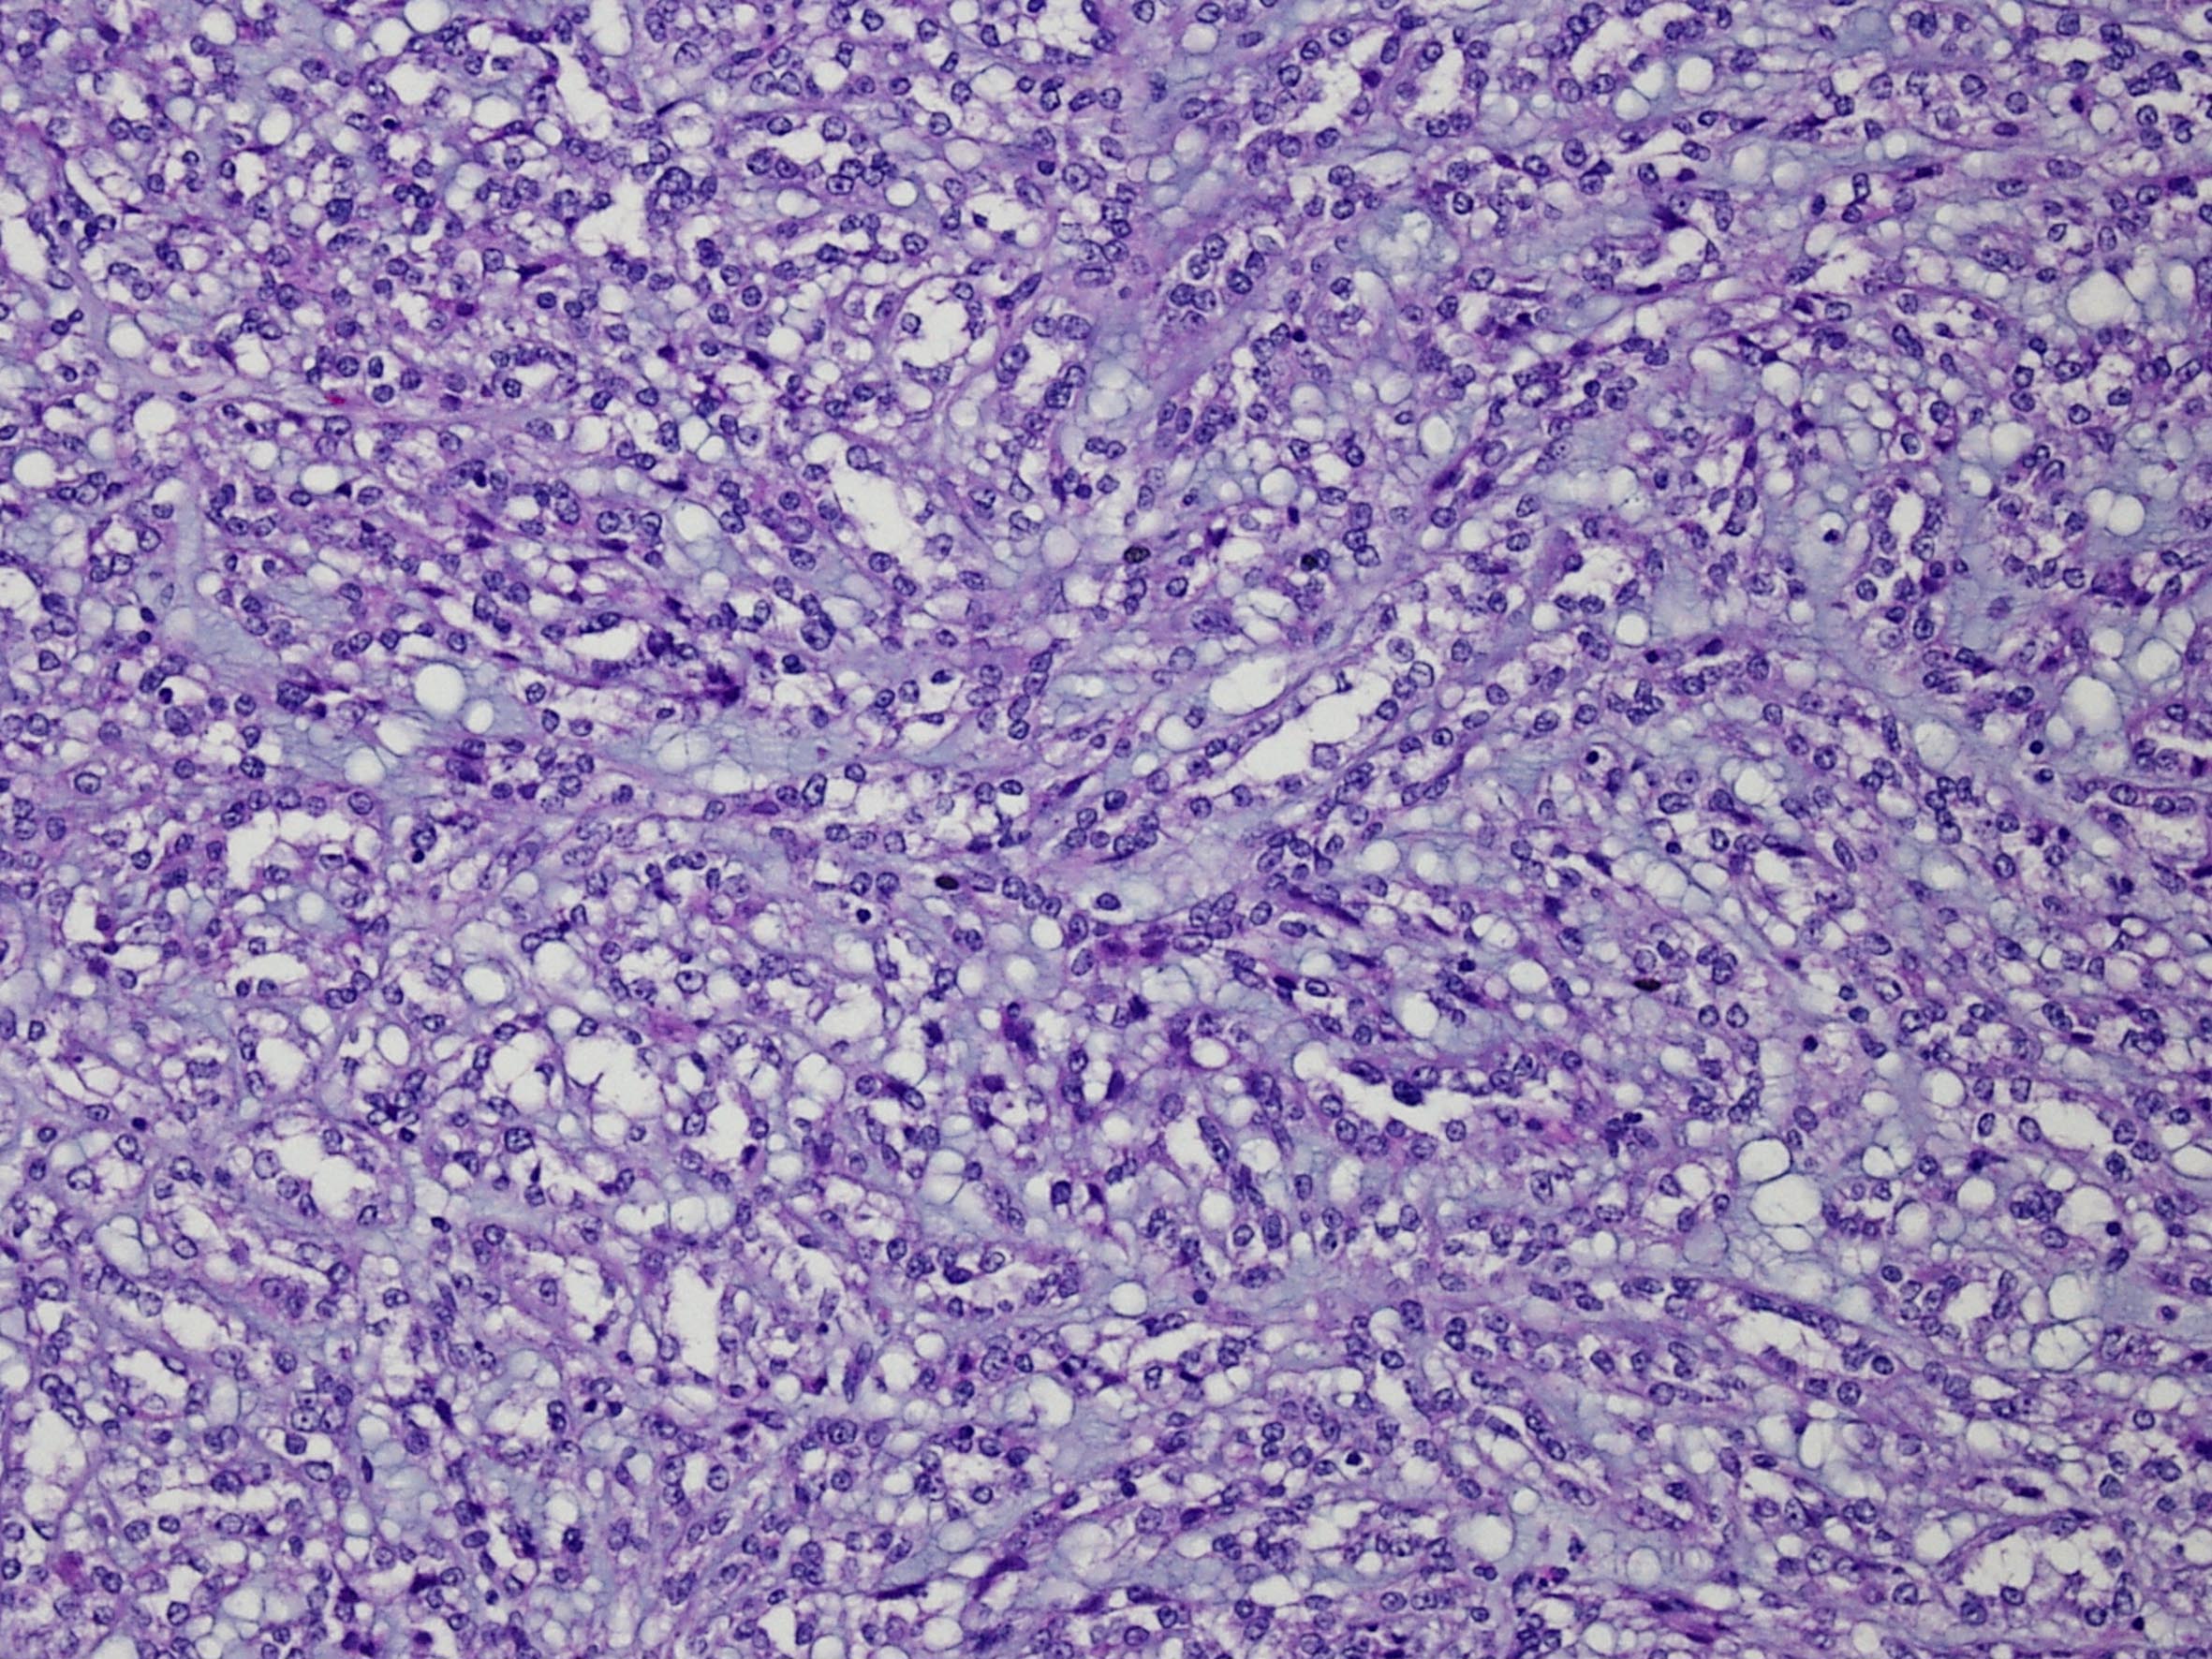

Classification of renal tumors

Case ID: 47